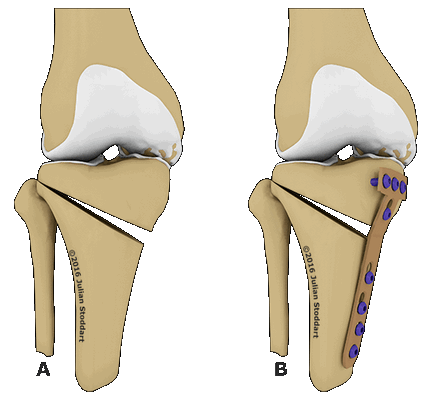

Рисунок 3 Рисунок 4 Рисунок 5 Рисунок 6 Рисунок 7 Рисунок 8

1 этап: проксимальная поперечная остеотомия малоберцовой кости:

- Выполните доступ к малоберцовой кости и удалите имеющиеся металлоконструкции. При необходимости удалите рубцовые ткани в области синдесмоза, обеспечив тем самым возможность удлинения малоберцовой кости (рис. 3)

- Выполните поперечную остеотомию на уровне бывшего перелома (рис. 4 и 5)

Рисунок 9 Рисунок 10 Рисунок 11

2 этап: репозиция и фиксация проксимальной поперечной остеотомии малоберцовой кости:

- Выберите подходящую пластинку и зафиксируйте ее дистально. С помощью техники «тяни-толкай» восстановите необходимую длину малоберцовой кости. Убедившись в восстановлении необходимой длины малоберцовой кости, зафиксируйте пластинку проксимально. Для временной фиксации пластинки можно использовать зажим (рис. 9 и 10)

- Фрагменты после дистракции утрачивают контакт друг с другом, поэтому образовавшийся дефект необходимо заместить опорным трансплантатом (рис. 11)

- Для фиксации трансплантата можно использовать дополнительную пластинку

- При данном типе операции синдесмоз обычно также нестабилен и нуждается в фиксации. С этой целью используется, как правило, не менее двух синдесмозных винтов

Схематичное изображение проведения операции.

Остеотомия с металлоконструкцией.